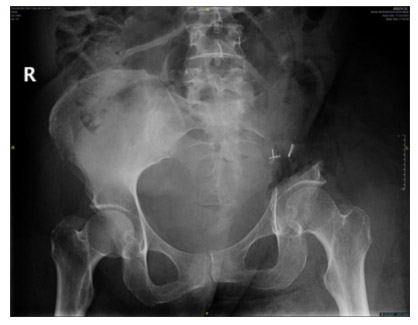

CASE 13: Cervical cancer metastasis to the left pelvic bone (sacroiliac joint)

Post-surgery: The X-ray shows a sacroiliac resection.